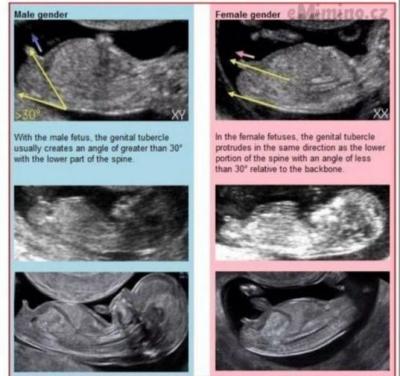

Holky, podle čeho to poznáte?😊🧡

@terezie90 Pohlavní hrbolek 😊